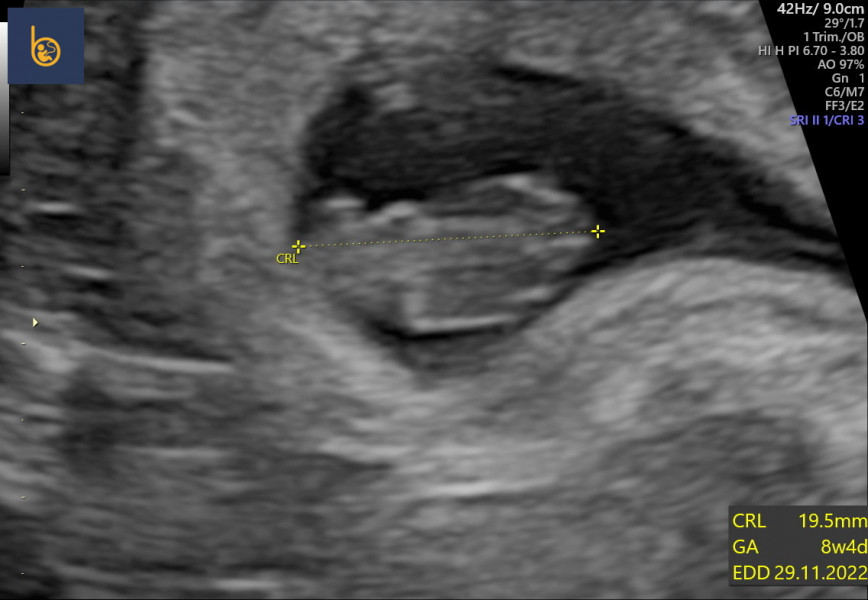

Went for our private scan today and baby was looking fab with a strong heartbeat! I'm 8+4 EDD now 29/11